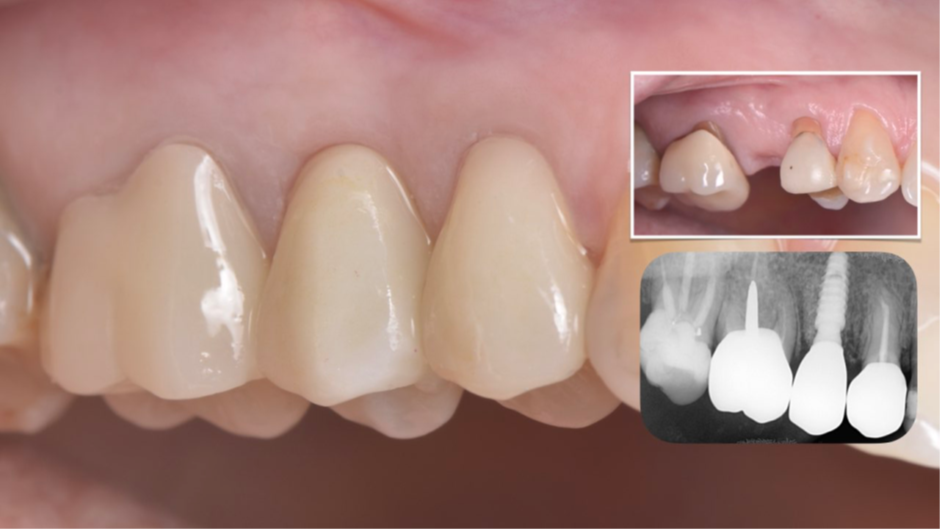

Após a finalização, os dentes adjacentes foram preparados e também receberam coroas provisórias, e a coroa sobre implante provisória foi parafusada no pilar Ideale (Figura 15) usando uma combinação de pressão digital e apertamento do paciente em um rolo de algodão. A isquemia dos tecidos moles peri-implantares pode ser observada, e geralmente desaparece em até 20 minutos. A coroa sobre implante provisória deve ser deixada por um período mínimo de um mês para permitir o adequado condicionamento dos tecidos moles peri-implantares 11,12 (Figura 16). Foi necessário um exame periódico para garantir que a higiene bucal adequada fosse mantida. Após dois meses, quando a mucosa condicionada se estabilizou 13, foi realizado um escaneamento intraoral (Figura 17) para a confecção das coroas definitivas (Figura 18). As coroas definitivas foram fabricadas fresadas em zircônia pura, e após instaladas (Figura 19), o resultado estético e funcional ficou muito favorável (Figura 20).

Figura 20 – Coroas definitivas finalizadas: imagem da situação inicial e radiografia periapical de controle imediatamente após a instalação.